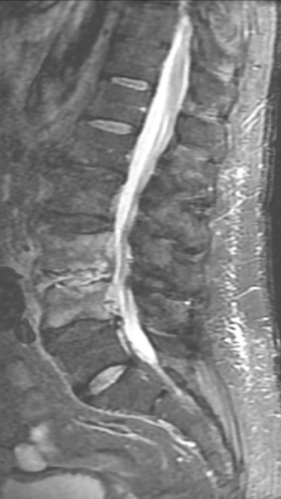

Спондилодисцит L3 – L4

4 процедуры ФДТ, 9 процедур MBST, 20 процедур ИПМТ

Параметры изменяются в зависимости от процедуры

Дата публикации: 22.08.2025 14:27:12